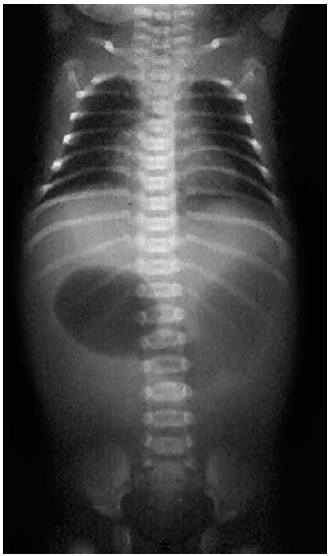

Recém-nascido, com um dia de vida, apresenta vômitos biliosos e distensão em epigástrio desde as primeiras horas de vida. O raio-X de abdome do paciente apresenta-se a seguir:

A principal hipótese diagnóstica e conduta cirúrgica são, respectivamente: